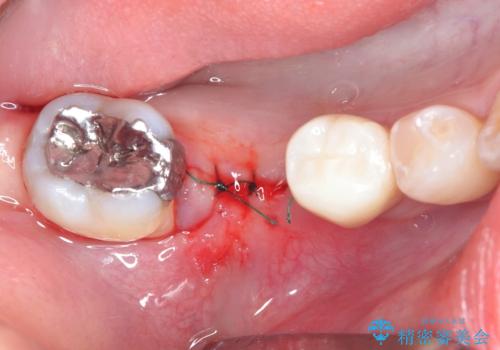

患者様の希望、ブリッジの土台となっている歯の状態、インプラントとブリッジの比較などを総合的に判断して、今回のケースではインプラント治療を選択しました。

- 外科手術のため、術後に痛みや腫れ、違和感を伴います

- 外科手術のため、術後に出血、痛みや腫れ、違和感を伴います